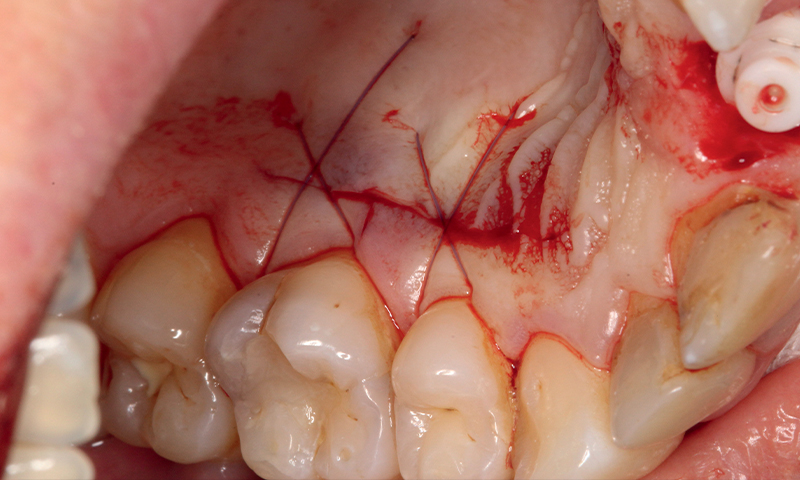

Fig. 14 (caso 3) - Decordo clinico dell'innesto di tessuto connettivo dopo l'inserimento dell'impianto

Caso 3: Un paziente maschio subiva un trauma durante l'infanzia e si presentava con una fistola associata al dente 11 e un difetto della cresta alveolare vestibolare. Il paziente era sottoposto a posizionamento immediato di un impianto SDS. In questo caso, l'aumento veniva combinato con il prelievo di tessuto connettivo subepiteliale (SCTG) dal palato, attraverso una singola incisione, tunnellizzazione buccale e inserimento dell’innesto. I successivi appuntamenti di follow-up rivelavano il successo della preservazione della cresta alveolare vestibolare, e della guarigione dei tessuti molli attorno all'impianto. L'osteointegrazione avveniva senza problemi e si poteva iniziare la pianificazione della corona definitiva. Questo caso era seguito per 5 anni e anche dopo questo periodo il contorno alveolare era estremamente soddisfacente. La guarigione e la gestione dei tessuti molli erano adeguate, suggerendo come l'applicazione dell'innesto di tessuto connettivo abbia contribuito positivamente al risultato estetico (Fig. 11-17).